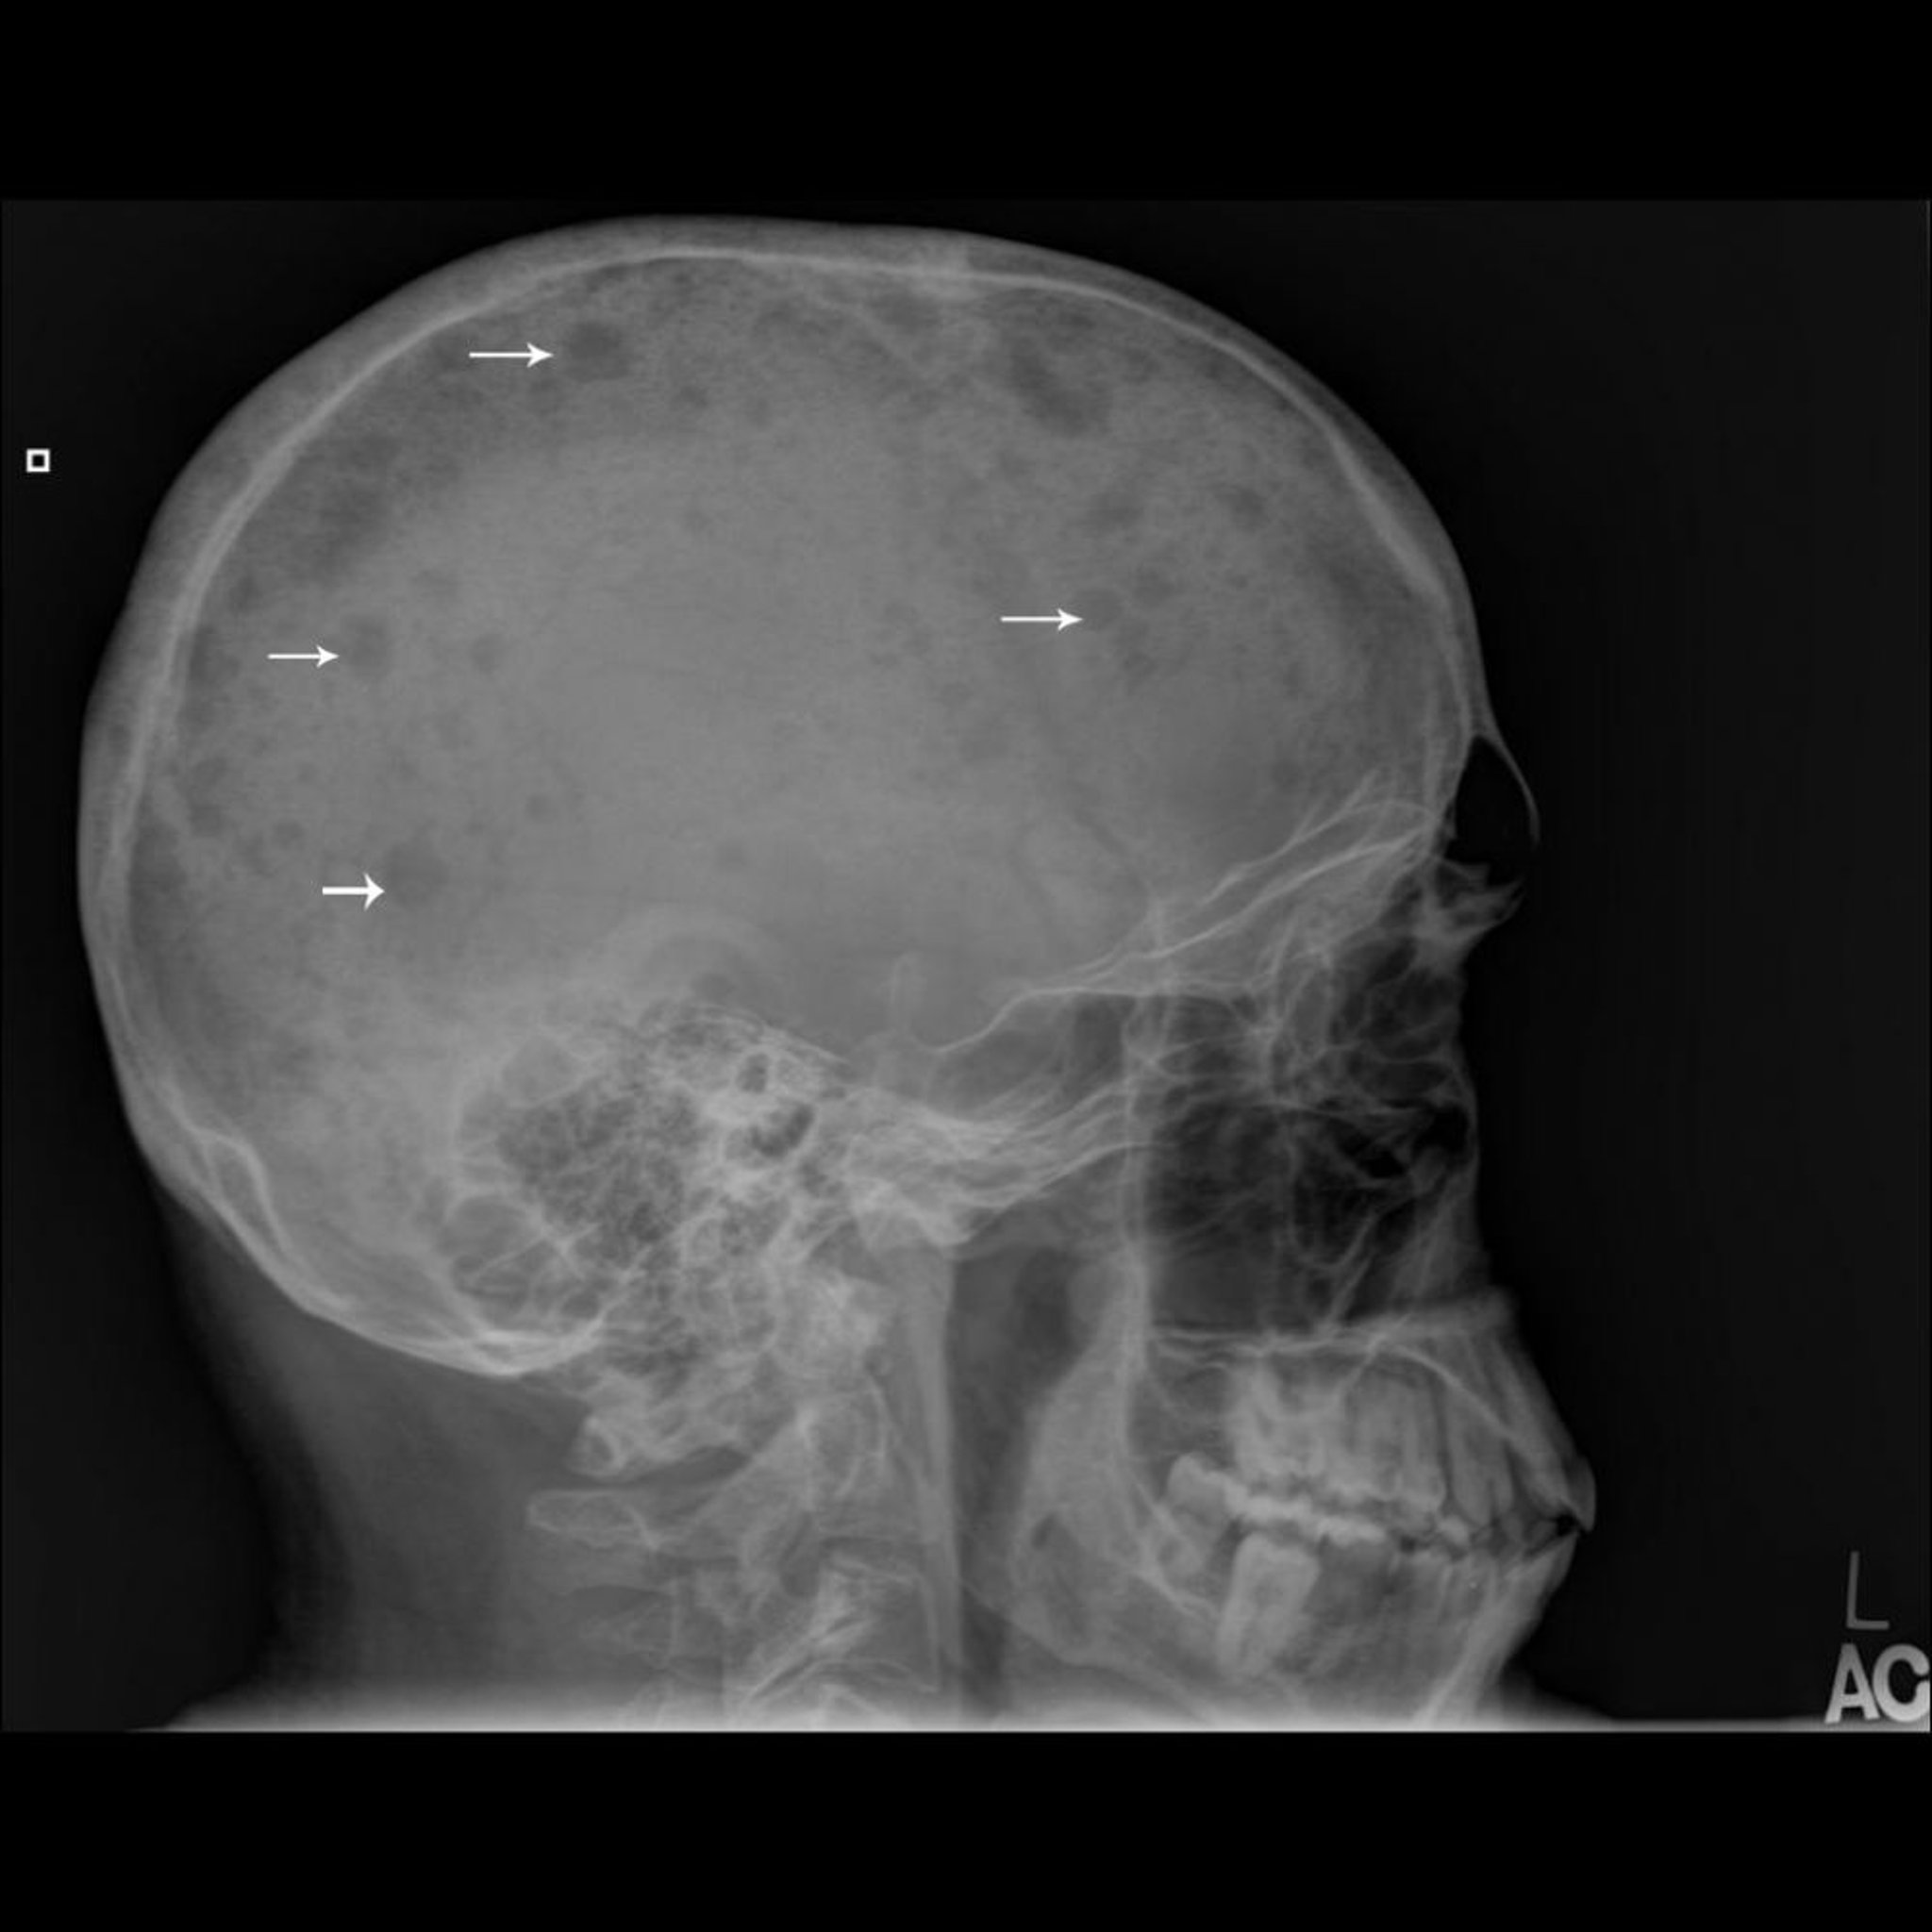

この頭蓋X線像では,多発性骨髄腫に典型的な骨の打ち抜き病変(矢印)が多数みられる。

Image courtesy of Michael J.Joyce, MD, and Hakan Ilaslan, MD.